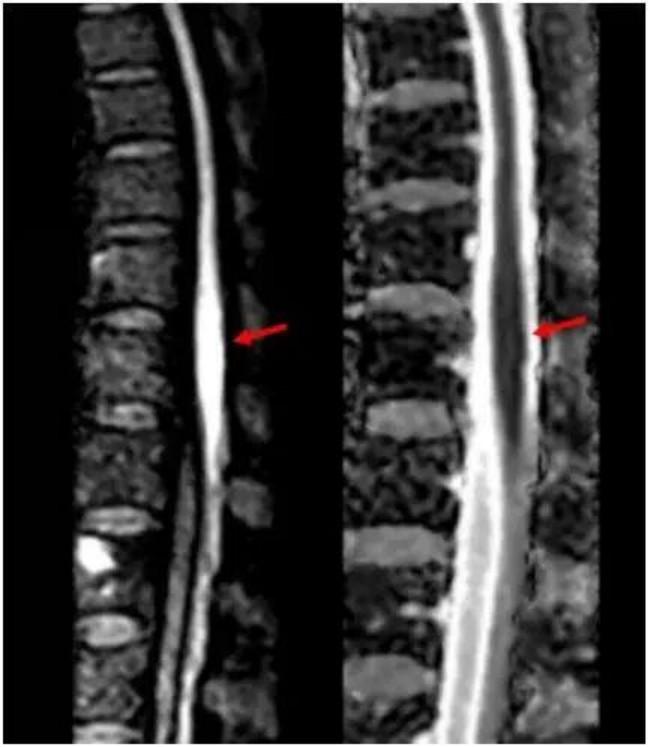

神经内科团队接诊后,凭借丰富临床经验,高度怀疑脊髓梗死。患者住院第2天早上,双下肢剧烈疼痛,很快完全瘫痪。主管护师逯红专查看患者后呼叫卒中救治团队。神经内科副主任医师刘效辉判断患者腰段脊髓再次梗死,科室迅速启动院内卒中绿色通道。医学影像科技师李峥根据神经系统查体确定的病变位置,调整扫描参数后对患者完善相关检查,磁共振影像结果显示患者脊髓圆锥存在弥散受限异常信号。医学影像科主任医师修建军阅片,确诊为脊髓梗死。超声医学科副主任医师包守刚进行超声检查排除主动脉夹层可能。

磁共振显示脊髓圆锥弥散受限,提示脊髓梗死